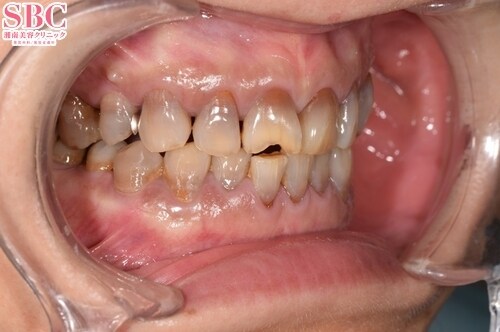

施術前

術前

40代

上の歯が欠けてしまったことと、虫歯や歯の変色などでお悩みのお客様です。テトラサイクリン歯と呼ばれ帯状に変色が見られます.